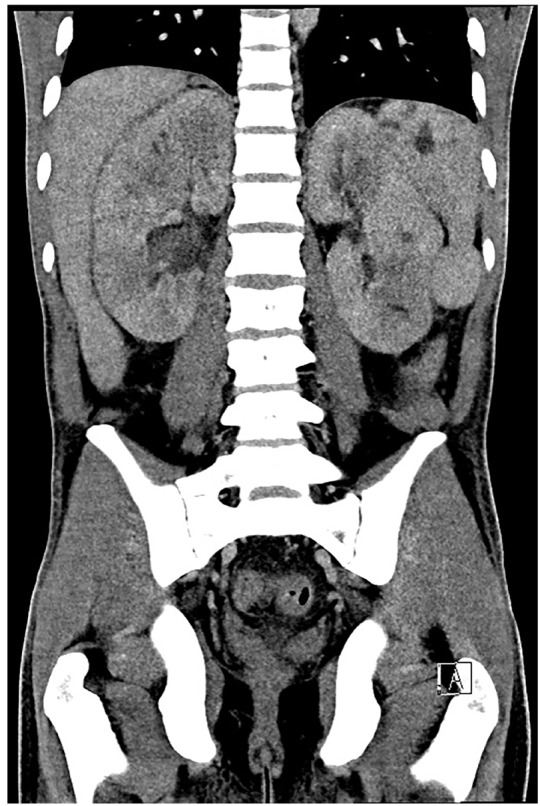

Although extrapulmonary Coccidioides infection is rare, it has been shown to disseminate to the skin and musculoskeletal system, with a strong affinity for bone. We present a case of disseminated Coccidioides infection with bone scintigraphy indicating diffuse fungemia despite equivocal serum assay, leading to appropriate antifungal therapy and a full recovery.